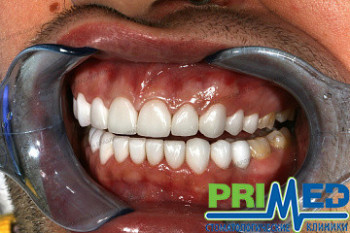

5 работ в портфолио

В своей практике доктор использует различные виды реставрационных материалов. Изготовление классических реставраций с металлическими и ДОЦ каркасами, так и цельнокерамических с использованием адгезивных технологий фиксации. Работа с мягкими тканями в эстетически значимой зоне, применение методик непосредственного послеоперационного протезирования, в т.ч. «немедленной нагрузки». В каждодневную практику доктора входит составление комплексных планов реабилитации стоматологических пациентов. В комплексный план входит как функциональная, так и эстетическая реабилитация пациента. Осуществление всех видов съемного и несъемного протезирования, в т.ч. с опорой на имплантаты. В своей практике доктор использует различные виды реставрационных материалов. Изготовление классических реставраций с металлическими и ДОЦ каркасами, так и цельнокерамических с использованием адгезивных технологий фиксации. Работа с мягкими тканями в эстетически значимой зоне, применение методик непосредственного послеоперационного протезирования, в т.ч. «немедленной нагрузки».